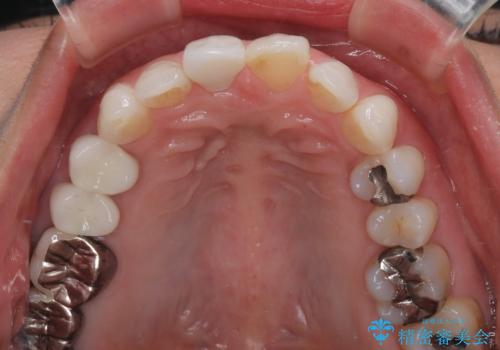

色がやや白いと感じましたが、ご自身でホームホワイトニングをされているそうで、今後周辺の歯を白くしていくとのことでした。

前歯に痛みがあるという実感はなかったそうですが、診察で叩いたときの痛みを感じた際、今までに同様の痛みや違和感を感じたことがあったとのことでした。

初回の根管治療で痛みや違和感は消退したため、その後は速やかに補綴治療を行いました。